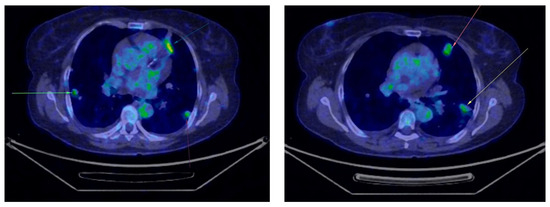

Five month later, the patient underwent her first follow-up PET-CT, which revealed multiple bilateral non-calcified pulmonary nodules, most of which showed minimal uptake, raising suspicion of secondary metastases (Figure 2). In the follow-up PET-CT performed six months later, multiple non-calcified nodules were observed bilaterally in the pulmonary parenchyma, with progressive dimensional and metabolic increases, the largest measuring 28/20 mm. These nodules were biopsied. The preliminary histopathological examination suggested carcinomatous infiltration, which was confirmed by the final histopathological report as clear cell carcinoma with pulmonary localization, indicative of secondary metastasis (Figure 3).

Figure 2.

First PET-CT revealing multiple bilateral non-calcified pulmonary nodules (marked in yellow and green circles).

Figure 3.

Second PET-CT scan showing the progression of the lung lesions (marked with arrows).